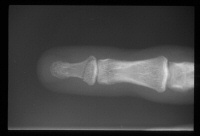

| Three months postop, after removal of prominent pins in the office. |

| Late appearance (ring finger) |